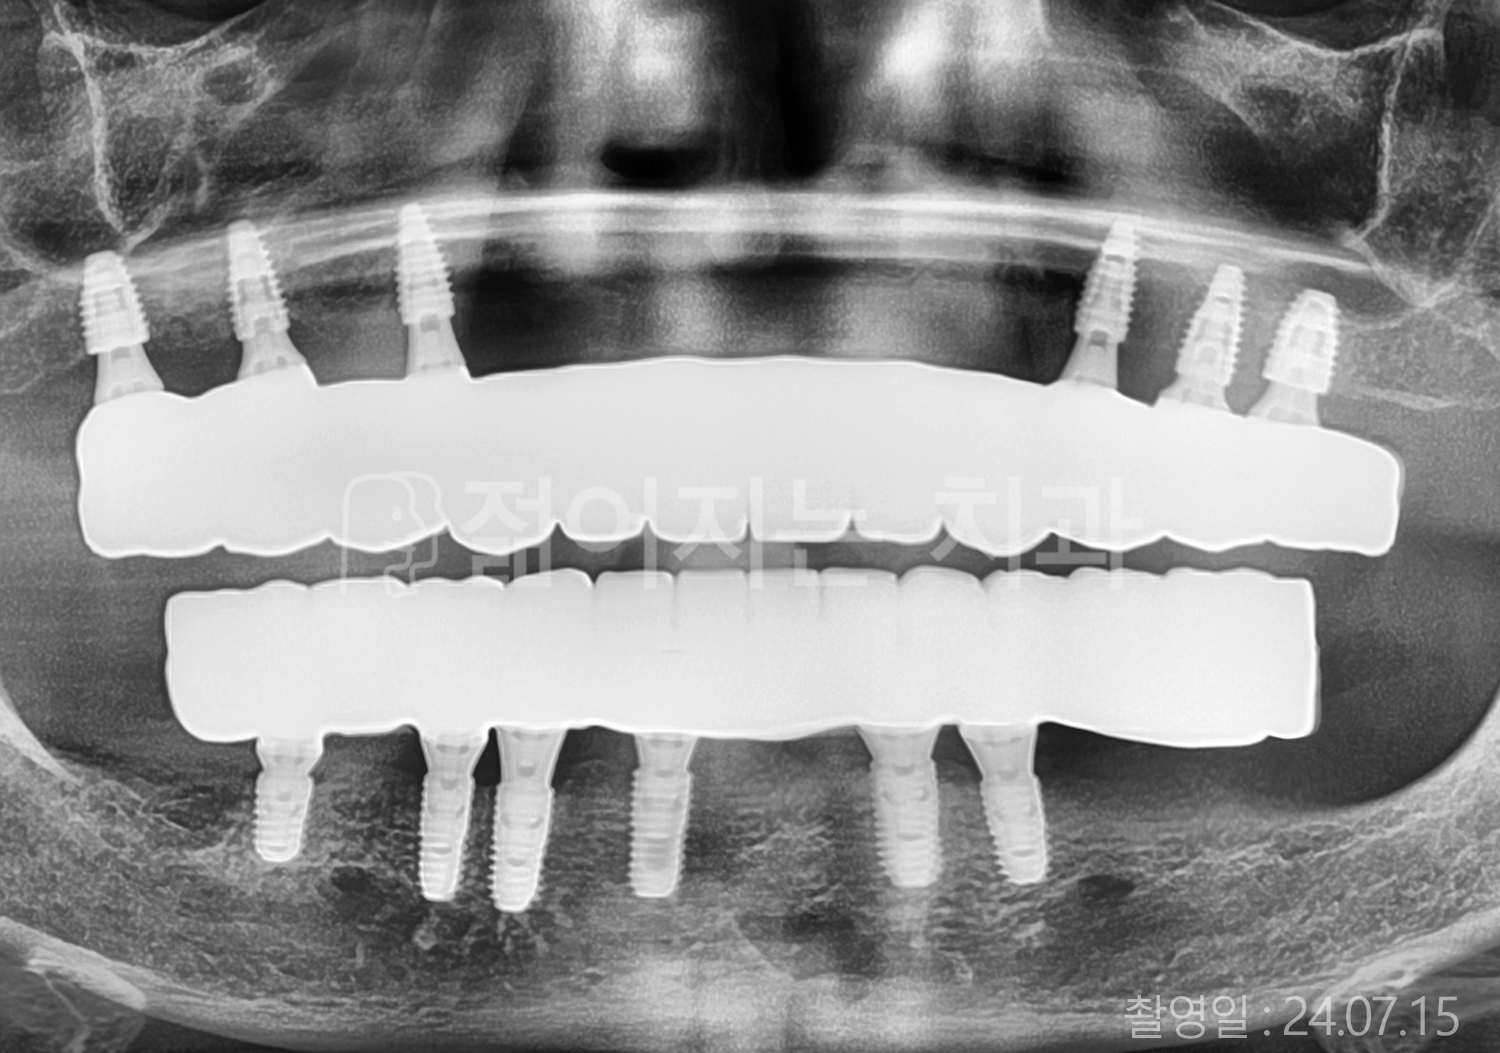

60대 고혈압, 고지혈증

전체치아 10개 이상 임플란트

60대 고혈압

70대 고혈압